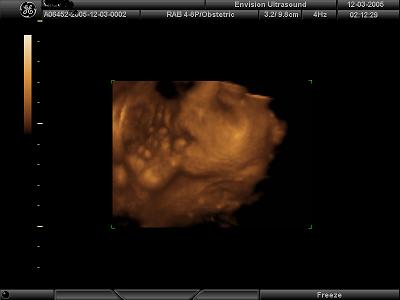

4D Ultrasound pics

We went to Envision in NJ yesterday to get our 4D ultrasound done for our 7 year wedding anniversary. It was the best gift we have ever given to each other!! Our little girl looks just like daddy but has mommys one dimple on her left cheek She is so beautiful and was playing with her umbilical cord the whole time trying to shove it in her little mouth. It was so fun to watch!! I would highly recommend getting it done. I posted my 4 fave pics out of 35 that we came home with and a lovely DVD set to music. Image Attachment(s):